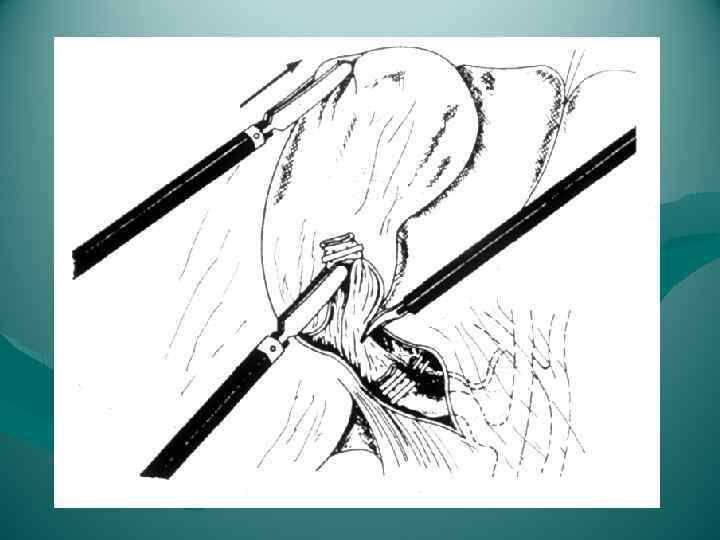

Раздавливание печени

Раздавливание печени